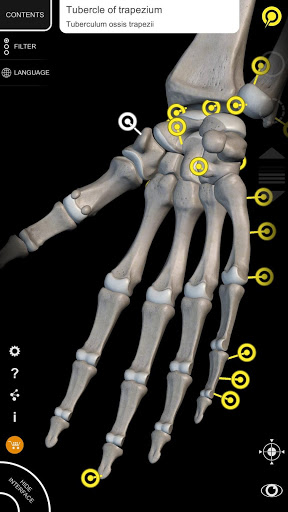

"Anatomy 3D Atlas" vous permet d'étudier l'anatomie humaine de manière simple et interactive.

Grâce à une interface simple et intuitive, il est possible d'observer chaque structure anatomique sous n'importe quel angle.

Les modèles anatomiques 3D sont particulièrement détaillés et avec des textures jusqu'à une résolution de 4k.

• Faites pivoter et zoomez chaque modèle dans l'espace 3D

• En sélectionnant un modèle ou une épingle, le terme anatomique associé apparaît